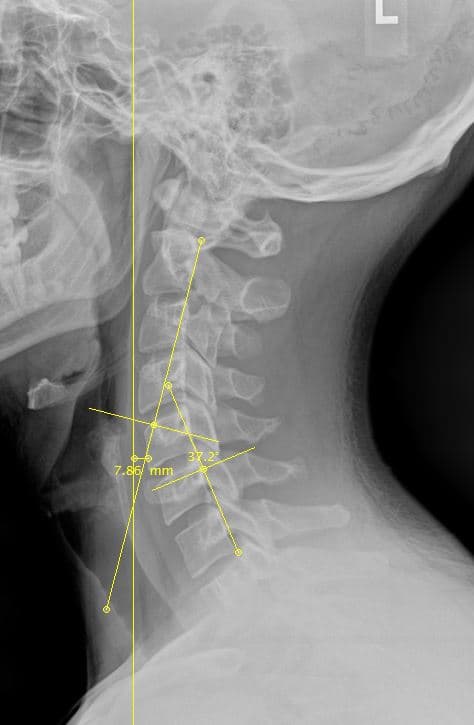

I just got done with my initial consultation and it was very amazing! They did x-rays and he saw exactly what was happening. I don’t think I’ve had an x-ray done yet since my car accident 1 year ago and he was really helpful, knowledgeable and found all the areas that he needs to work on for me to get fully recovered. The team have all been very respectful, curious and empathetic. Thank you so much!